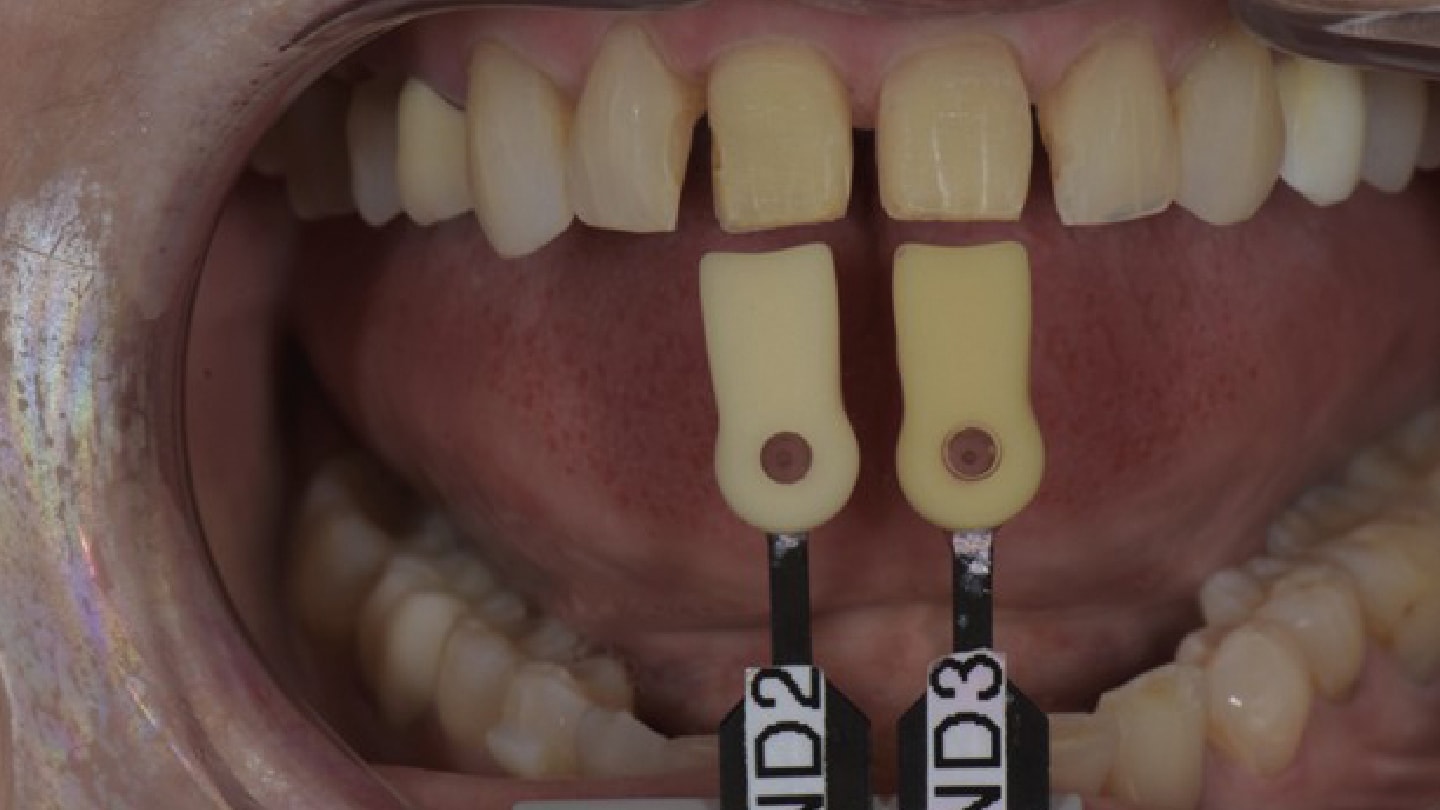

The final restorations were received from the laboratory and the patient scheduled for a try-in appointment. The patient was anesthetized, and a lip and cheek retractor was placed (OptraGate, Ivoclar). The provisional restorations were carefully removed and excess debris on the preparations removed. A translucent try-in paste (Choice 2, BISCO) was applied to the veneers and the restorations seated. Once seated it became apparent the veneers were too bright in value midfacial to incisal. Although the patient initially approved the finals, the clinician insisted they be sent back. The veneers were returned to the laboratory along with images of shade tabs of the temporary material and polarized images taken to communicate the value of adjacent teeth (Figure 19 through Figure 21). Temporary restorations were once again fabricated chairside and placed. A week later the second set of final restorations arrived from the laboratory and the try-in protocols repeated (Figure 22).